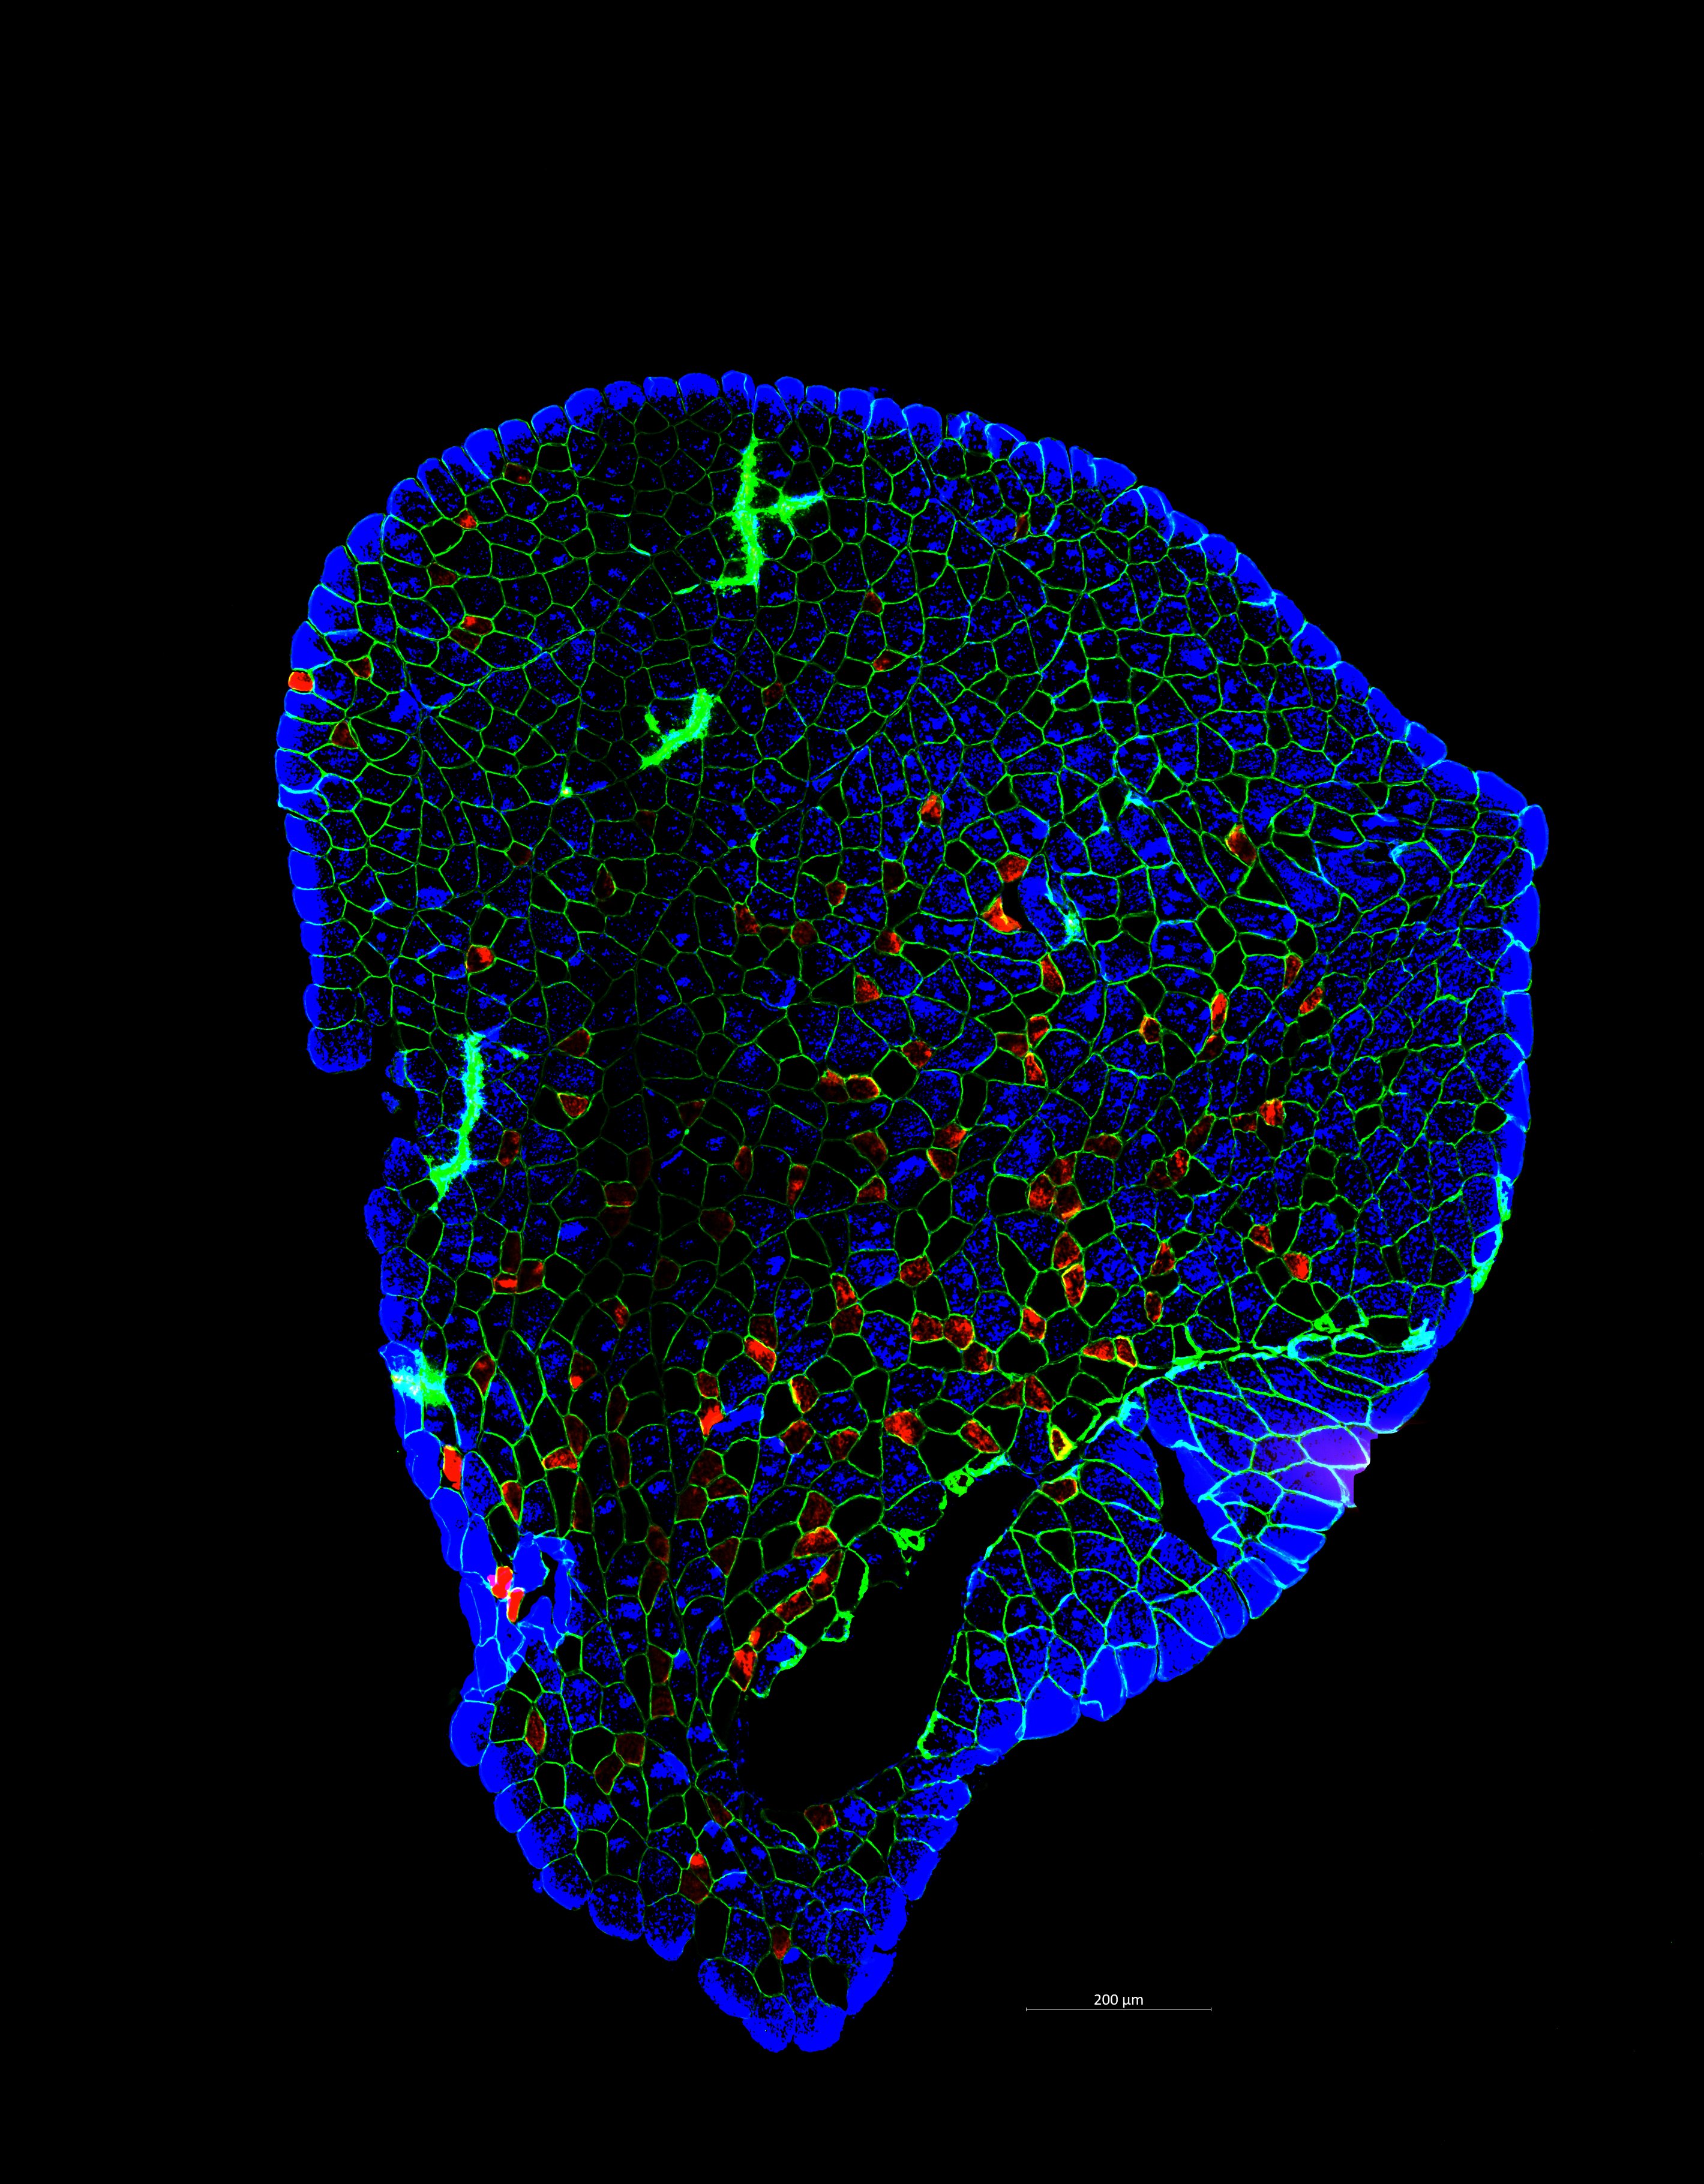

Immunofluorescence of mice liver sections with nuclei (blue) and zonal markers E-cadherin (periportal, yellow) and glutamine synthetase (pericentral, red). The liver helps maintain metabolic processes, hormone production, nutrient storage, and detoxification. This happens when the oxygen and nutrient-rich blood flow from the periportal vein to the pericentral vein in the liver lobule, the functional unit of liver.  As a result, the blood flow creates a gradient of oxygen, nutrients and signaling molecules, creating three different zones in the liver lobule. These zones have different functions, and they express different proteins depending on their functions. Here, we have used Glutamine synthetase (red) to view the pericentral zone and E-cadherin (yellow) for the periportal zone to study the zonation.